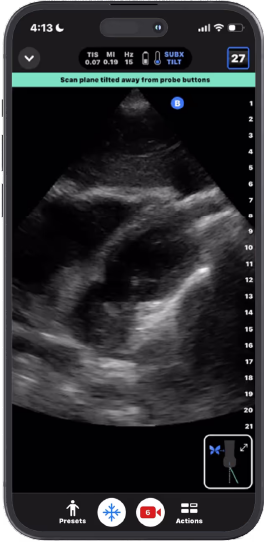

Inclinação subxifoide™

Esse recurso inclina o feixe para facilitar a captura da imagem, reduzindo a necessidade de um ângulo raso e possível pressão para visualização.